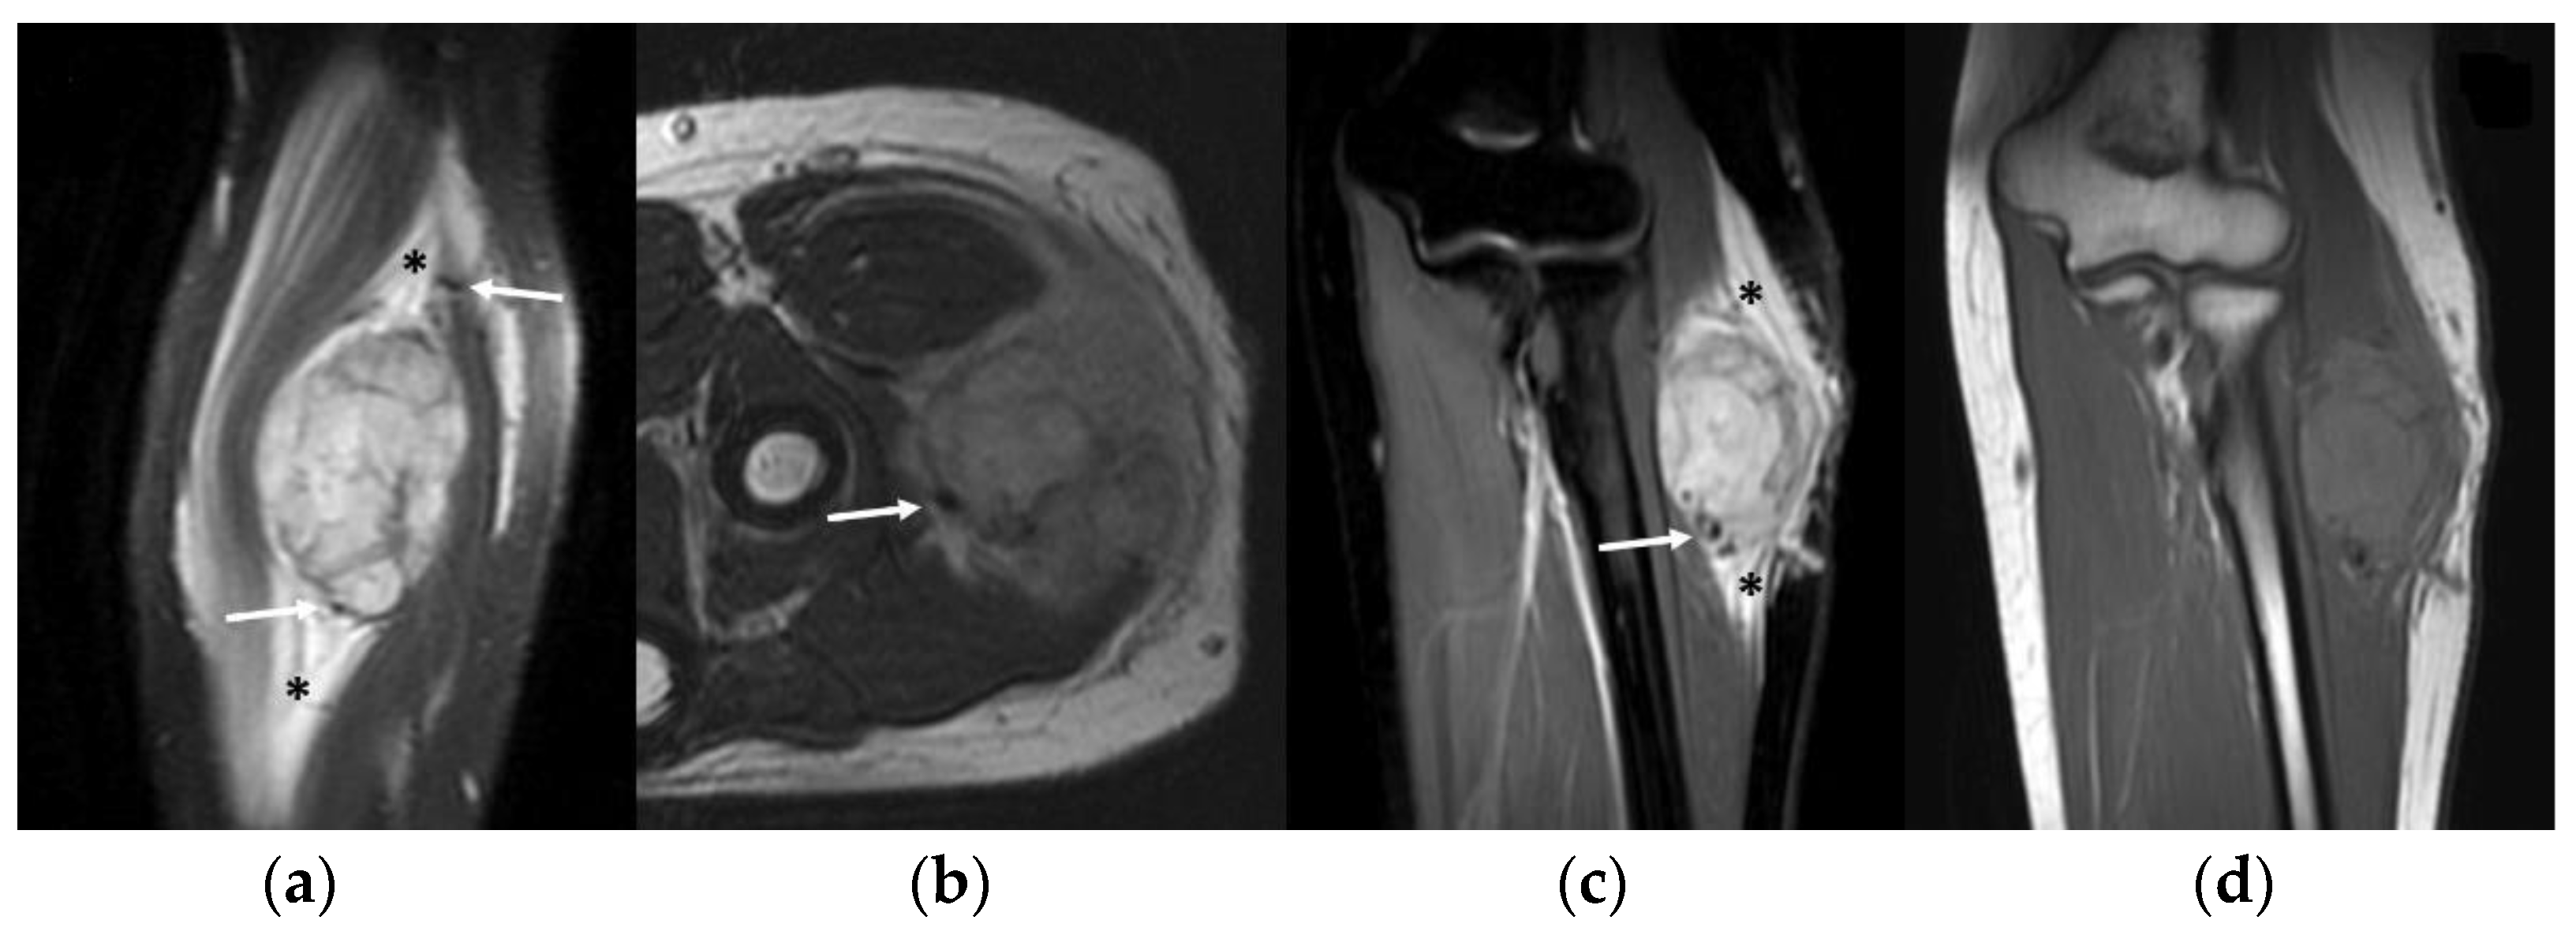

3.4. MRI Features

- Slight hyperintense MRI signal on T1-WI and a moderately inhomogeneous hyperintense signal on T2-WI

- MRI flow voids on fluid-sensitive sequences

- MRI peritumoral edema